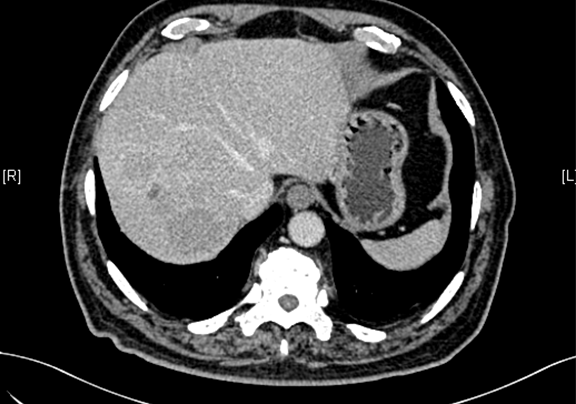

下腹部增强CT示:肝右后叶上段占位,肝癌可能性大;右侧肾上腺占位,不除外转移瘤。

术前CT检查:

动脉期

静脉期

平衡期